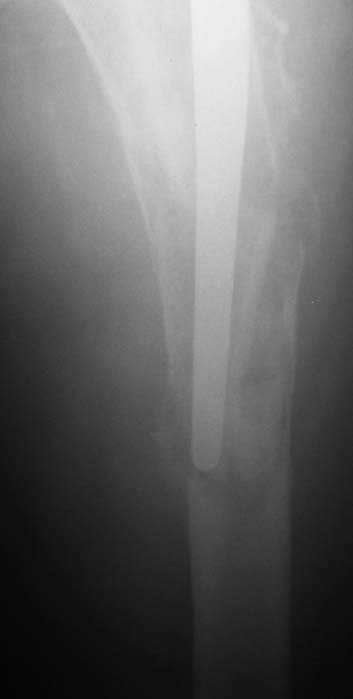

Мужчина, 39 лет.По поводу двустороннего асептического некроза головок бедренных костей последовательно выполнено тотальное эндопроезирование левого (1998 г), затем правого (1999 г) тазобедренных суставов.

С 2001 г отмечает нарастающие боли в левом бедре. Предполагается удаление протеза, удаление цемена из канала бедра, пластика дефекта бедренной кости.

Нет никакого смысла делать операцию в два этапа. С чашкой все понятно - стандартный подход с установкой пресс-фит компонента. На бедре имеет

место перипротезный перелом В3 типа - т.е. перелом вокруг ножки с ее нестабильностью на фоне выраженного остеолиза. Решение - доступ к каналу

через перелом с удалением самой ножки, костного цемента и рубцовых тканей. Установка ножки дистальной фиксации (типа Solution), длину ножки

надо определить по шаблону. Минимальный контакт ножки с интактной костью - 6-8 см. Фрагменты проксмального отдела собираются на ножке

эндопротеза, дефекты костной ткани заполняются чипсами (аллографт) и фиксируются кортикальными аллографтами, уложенными дополнительно по типу

"вязанки хвороста" серкляжом. Мы имеем 8 или 10 подобных наблюдений и результатами довольны.